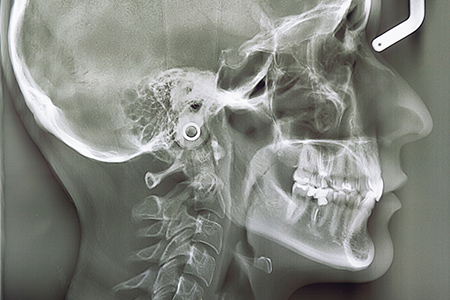

港区赤坂・赤坂見附の矯正歯科「赤坂B&S歯科・矯正歯科」では、患者さんにより正確で不安の少ない矯正治療を提供するために、先端の「3Dデジタル矯正システム」を導入しています。口腔内スキャナーとコーンビームCTスキャナ(CBCT)を使用して、患者さんの歯並びや顎、顔面の骨格を読み取り、コンピューター上で正確に再現・シミュレーションを行えるのが特徴です。さまざまな角度から歯並びを確認することで、従来の2次元のレントゲン写真に比べて、より質の高いシミュレーションが可能です。精度の高いシミュレーションにより、効率的かつ効果的に歯を移動させることができるため、より良好な結果が期待できます。

矯正歯科診断には通常、頭の骨のレントゲンであるセファログラムが使用され、矯正治療を行う医院では必須の資料となっています。このレントゲンを用いて横顔や正面の骨の状態を分析し、治療方針を策定します。しかし、2次元の情報だけでは限界があり、3次元の情報が必要であることがわかってきました。

しかし、2次元の情報だけでは歯の配置を正確に評価するのは難しく、足りないスペースが抜歯を必要とする場合もあります。3次元データを使用することで、より正確な診断と治療計画が可能となり、抜歯を回避することもできます。これにより、矯正治療の質が向上し、患者さんにとってより良い結果につながる可能性が高まります。